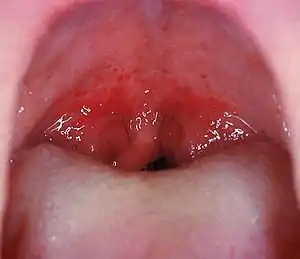

When group A streptococcal infects the throat, it is also known as streptococcal pharyngitis, or strep throat. Redness, trouble swallowing, swelling of regional lymph nodes, and localized pain are common complaints of streptococcal pharyngitis. Leukocytosis, an abnormally high white blood level, is a common reaction to the infection. Streptococcal pharyngitis is most prevalent during colder seasons. Many marching bands play on cold nights at football games. Exposing musicians to such weather and bacterium may increase the likelihood of infection[6].